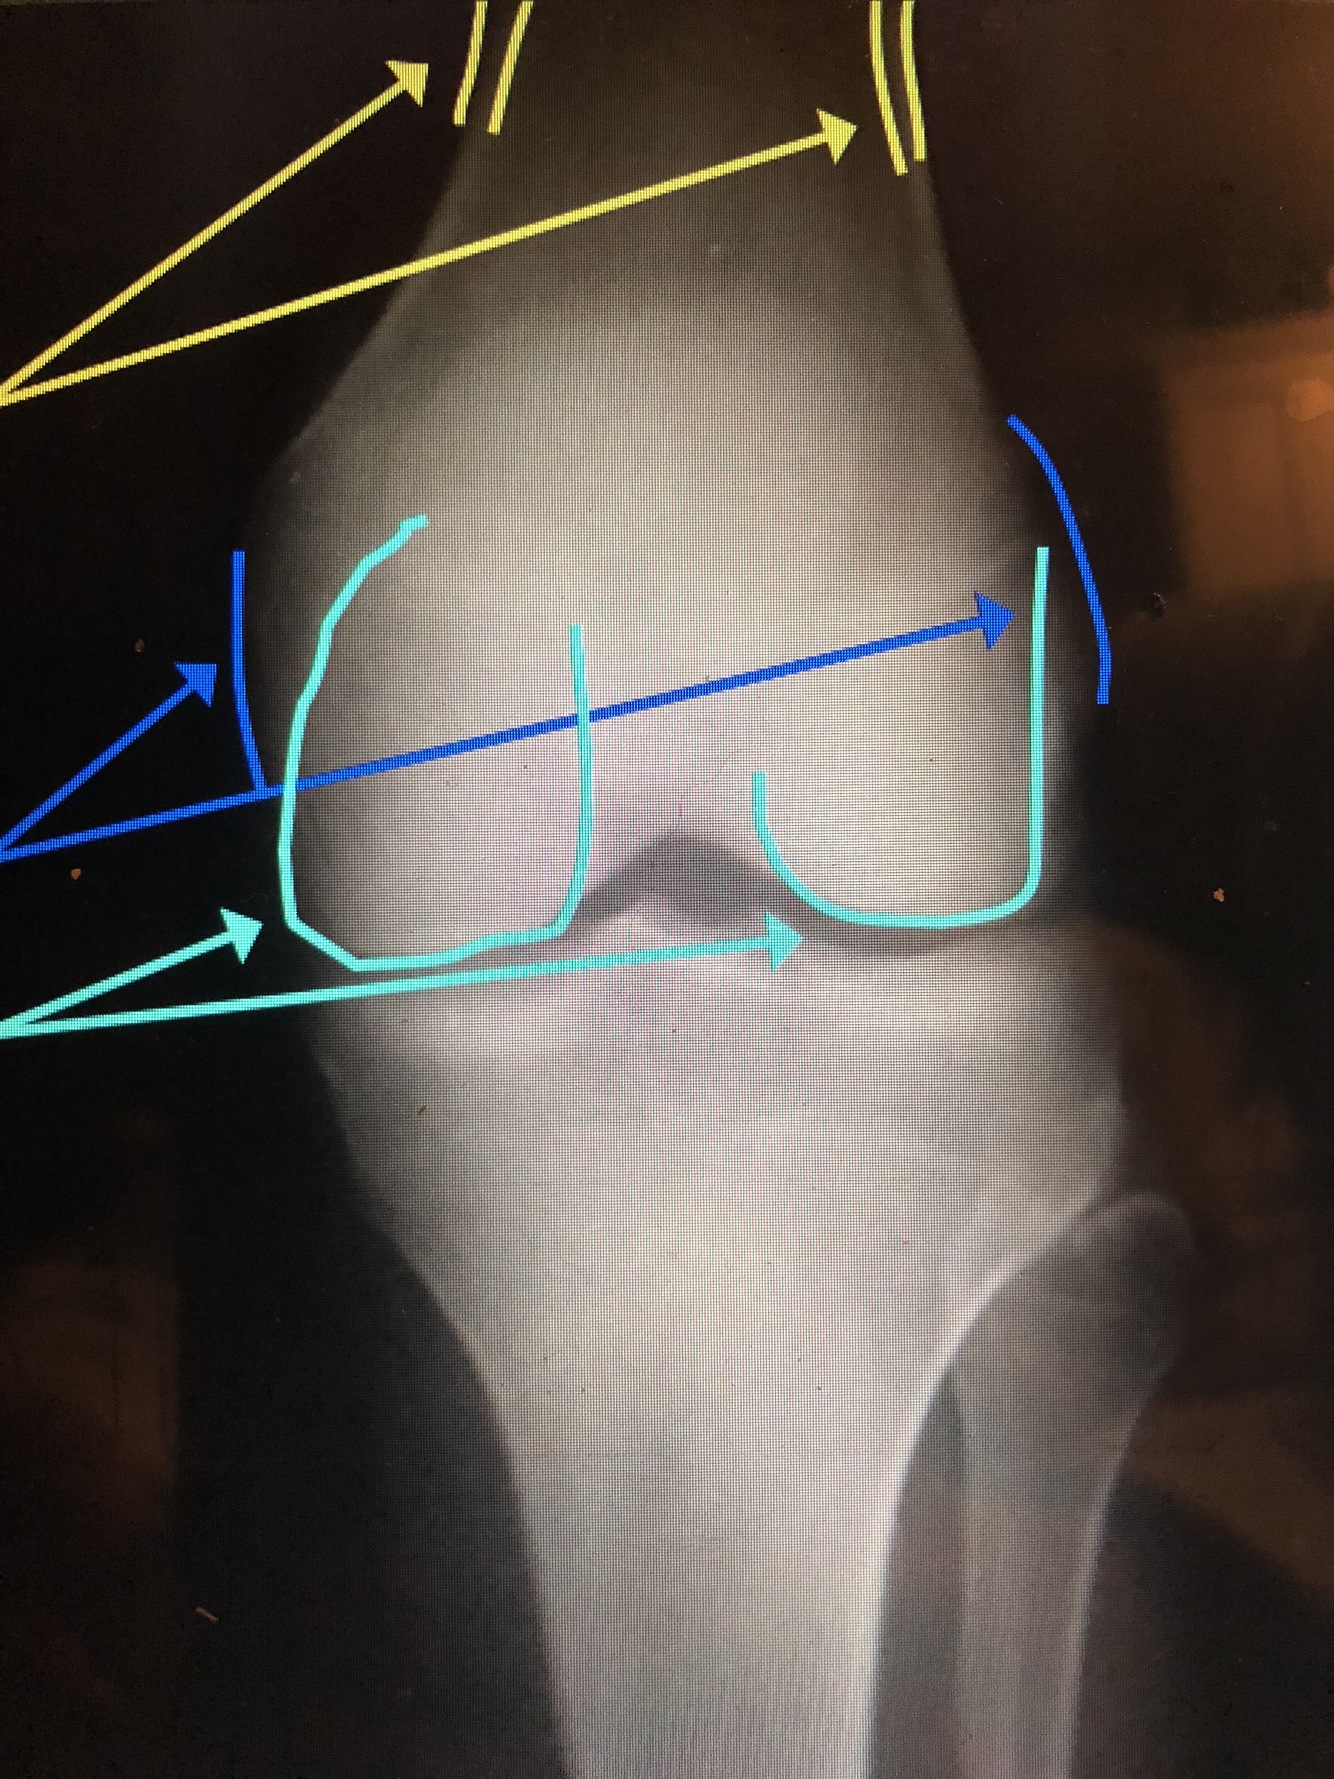

What is the light blue line?

Lateral Femoral Condyle

•Usually projects more proximally and is smaller

What is the yellow line?

Medial Femoral Condyle

•Usually is larger and is projected more distally

Cortex – thickest at the diaphysis, but thins out near the metaphysis at the epicondyles

Q

Epicondyles (med. & lat.)

what is the light blue lines?

Femoral Condyles (med. & lat.)

What are the yellow lines?

Supracondylar Ridge/Line (med. & lat.)

Adductor Tubercle

What is the dark blue line?

Intercondylar Notch